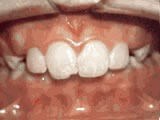

Patient started treatment at age 11 and wore braces for 26 months. He loves his new smile.